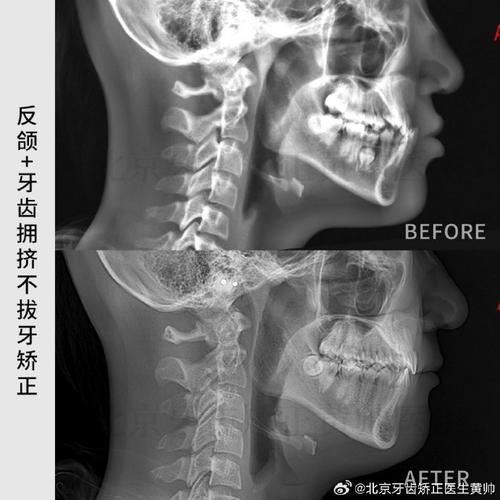

正畸侧位片是口腔正畸诊疗中不可或缺的影像学检查手段,通过头颅侧位影像系统分析颅面骨骼、牙齿排列及软组织形态,为错颌畸形的分类、诊断、方案制定及疗效评估提供客观依据,在临床实践中,其核心价值在于通过精准的标志点定位与测量,量化评估颅面结构的三维关系,77分析体系”(通常指7个核心骨骼标志点与7个核心牙齿标志点的组合)是侧位片解读的基础,这些标志点的精确定位直接关系到后续诊断的准确性。

正畸侧位片的拍摄需严格遵循标准化流程:患者采用自然头位,眶耳平面(由眶下缘最低点与外耳道上缘连线构成)与地面平行,X线中心线对准外耳道上方5cm处,胶片或探测器距离中矢面15cm,曝光参数根据患者年龄及体型调整(成人通常为60-70kVp,8-15mA),确保图像清晰显示颅骨轮廓、颌骨形态、牙齿牙根及周围骨结构,避免因头部倾斜、咬合干扰或伪影导致标志点模糊。

- ANB角:由上齿槽座点(A)、鼻根点(N)、下齿槽座点(B)构成,正常值2°±2°,是判断上下颌骨矢状关系的关键指标,ANB角>4°提示Ⅱ类骨性错颌(上颌前突或下颌后缩),<0°提示Ⅲ类骨性错颌(下颌前突或上颌后缩)。

- SN-Me角:由蝶鞍点(S)、鼻根点(N)、颏下点(Me)构成,正常值68°±5°,反映下颌平面(通过Me点与下颌角点的连线)相对于颅底平面的倾斜度,角度增大提示下颌平面陡峭,面部垂直高度增加;减小提示下颌平面平缓,面部垂直高度不足。

正畸侧位片通过“77分析体系”的量化数据,可实现:①错颌畸形分类(骨性Ⅰ、Ⅱ、Ⅲ类,牙性深覆颌、深覆盖等);②制定个性化矫治方案(如拔牙与否、种植支抗设计、隐形矫治方案规划);③预测矫治后效果(通过计算机模拟分析骨骼、牙齿移动后的位置变化);④评估治疗后稳定性(对比治疗前后指标变化,防止复发),对于ANB角>4°的Ⅱ类错颌患者,若同时伴有U1-NA距过大,需设计上颌磨牙后移、切牙内收的方案;对于SN-Me角过大的垂直生长型患者,需避免使用垂直向牵引,以防面高进一步增加。